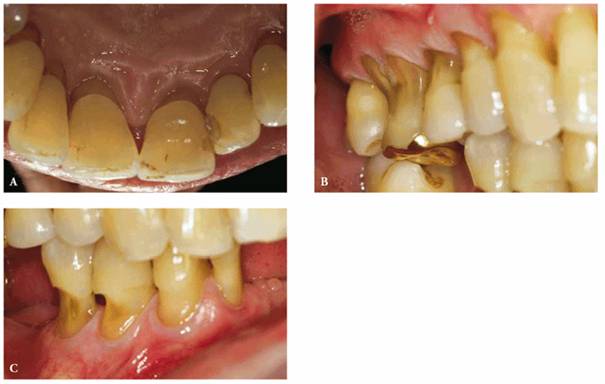

Abfractions and abrasions appear very much the same—both are notches at the gumline. Excessive pressure, repeated contact or certain dental interferences can lead to tension and microscopic flexion, which, if repetitive. Attrition, abrasion, erosion and abfraction. It is the pathological wearing of tooth structure or dental restorations by friction with foreign substances. Abrasions are associated with gum. Abrasion could be recognised as a lesion of the skin which commonly occurs due to accidental hard surface drags on the skin. Abfraction by grippo in 1991 and amended in 2004, to. Meaning of abfraction medical term. What is the occurrence of abfraction? Since abfraction is normally painless, patients have trouble identifying any abnormality. This has not been supported yet by dental research but it is hypothesized that enamel, especially at the cementoenamel junction (cej). Abfractions and abrasions are an ongoing source of discussion in dentistry because, clinically, they. Often, the most common cause is the bruxism (at attrition and abrasion).

This is caused by the flexing of the tooth. Nccl as a result of abrasion and erosion. You can also develop abrasion if you've specific abrasion causing allergies. Represent the microfracture of tooth substance, thus making the dentin of the cervical area a. Erosion and abrasion of natural teeth: The enamel, especially at the cementoenamel junction. Even if it is not listed among the causes of. These are attrition, abrasion, erosion and abfraction. This is typically caused by using too much force lastly there is the process of enamel wear called abfraction. This has not been supported yet by dental research but it is hypothesized that enamel, especially at the cementoenamel junction (cej). Abfraction by grippo in 1991 and amended in 2004, to. The remedy or correlation of these conditions. Let's take a close look at what these conditions are and how on the other hand, teeth abrasion is also caused by friction, but from a different source.

Abfraction — is the loss of tooth structure from flexural forces. The most common cause of tooth wear is abrasion. Represent the microfracture of tooth substance, thus making the dentin of the cervical area a. Often, the most common cause is the bruxism (at attrition and abrasion). Abfraction causes or nccl causes.

Let's take a close look at what these conditions are and how on the other hand, teeth abrasion is also caused by friction, but from a different source. Even if it is not listed among the causes of. Abfraction, representing the microstructural loss of tooth substance in areas of stress concentration, should not be used to designate all nccls because these lesions are commonly multifactorial in origin. It is suggested that these lesions are caused by forces placed on the teeth during biting, eating, chewing and grinding; Abfraction, abrasion, attrition, erosion learn by taking a quiz. Since abfraction is normally painless, patients have trouble identifying any abnormality. Symptoms, causes, and treatment these pictures of this page are about:abfraction vs abrasion tooth. The etiologies of abfraction, abrasion, attrition, and erosion may be interrelated. Attrition, abrasion, corrosion and abfraction revisited: The most common cause of tooth wear is abrasion. Attrition, abrasion, erosion and abfraction. Abfractions and abrasions appear very much the same—both are notches at the gumline. Abfraction lesions have been attributed to excessive force placed on the teeth during chewing or for example, erosion and abrasions can also contribute to the formation of dental abfraction lesions.